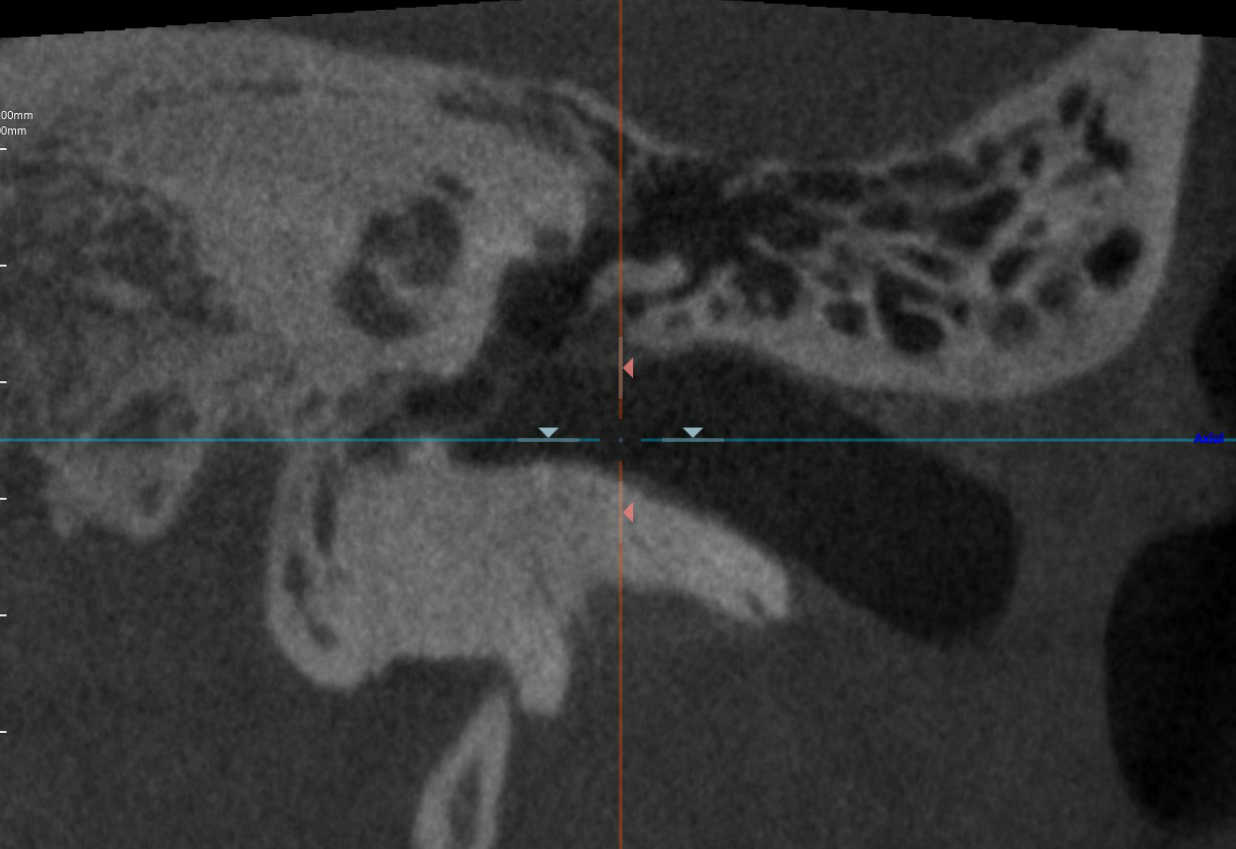

中耳CT